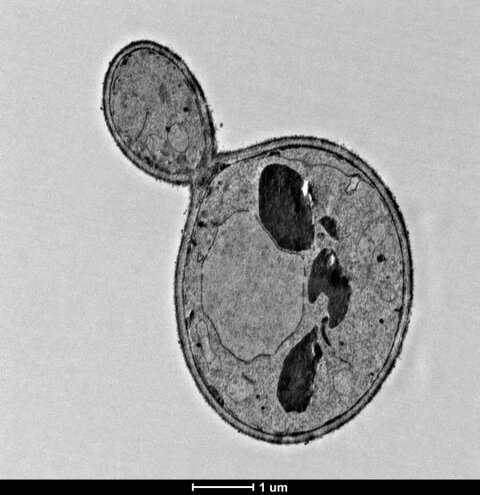

2. Transmission Electron Microscopy Processing unit

Electron Microscopy (EM): Basically two types:

1. Transmission Electron Microscope2. Scanning Electron Microscope